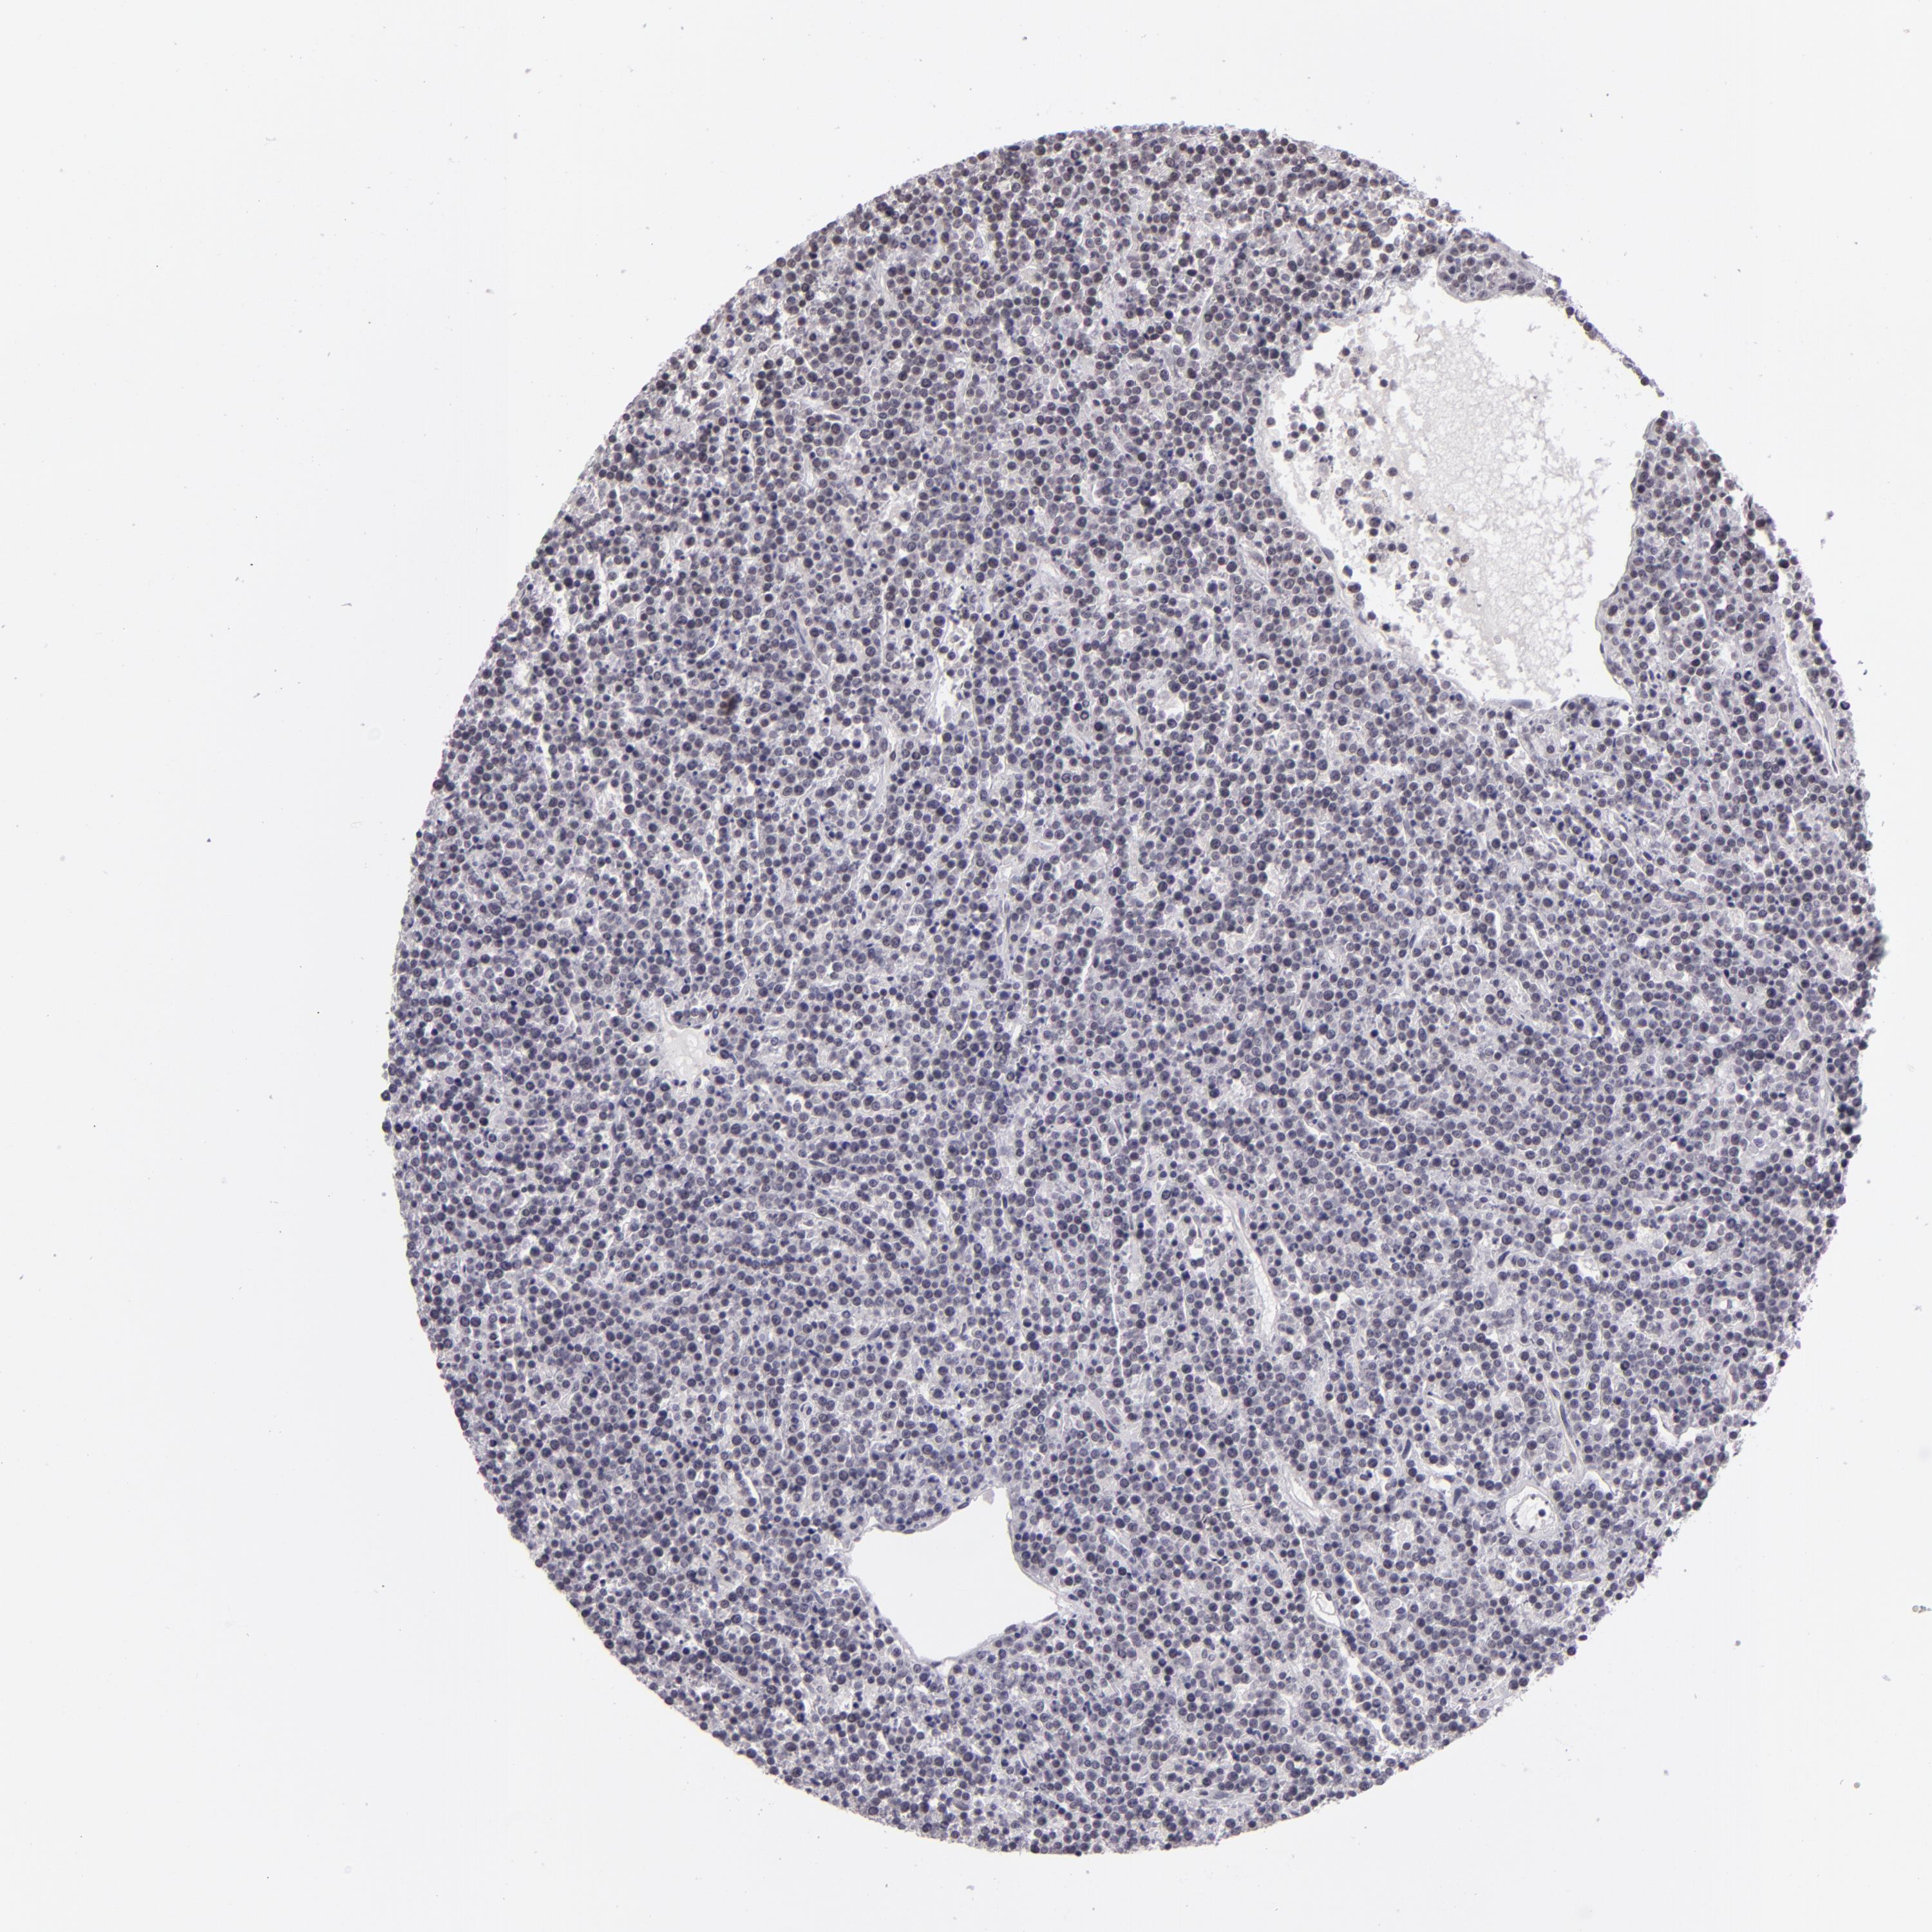

LYMPHOMA - Protein expressioni

A mouse-over function shows sample information and annotation data. Click on an image to view it in a full screen mode. Samples can be filtered based on level of antibody staining by selecting one or several of the following categories: high, medium, low and not detected. The assay and annotation is described here.

Each image is clickable and will lead to virtual microscopy that enables deeper exploration of all samples and also displays staining intensity scores, fraction scores and subcellular localization as well as patient and tissue information for each sample.

Antibody HPA001791

Staining

High

Medium

Low

Not detected

Intensity

Strong

Moderate

Weak

Negative

Quantity

>75%

75%-25%

<25%

None

Location

Nuclear

Cytoplasmic/membranous

Cytoplasmic/membranous,nuclear

Malignant lymphoma, non-Hodgkin's type, High grade

Hodgkin's disease, NOS

Malignant lymphoma, non-Hodgkin's type, Low grade